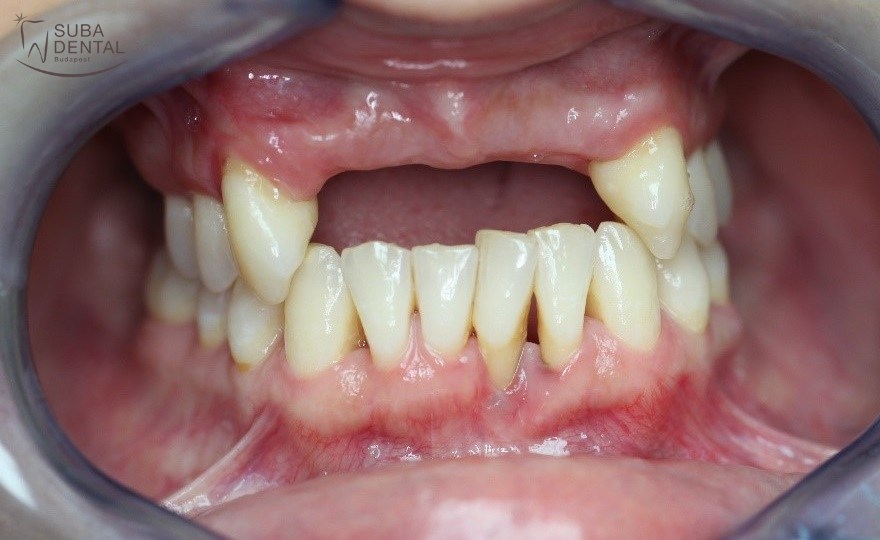

A gyógyult íny a foghúzások helyén a gyógyulási időt követően

Előtte

Utána